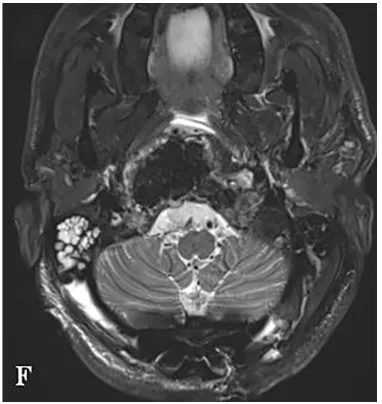

术前MRI显示,肿瘤呈浸润性生长,并向双侧后外侧扩展,右侧受累尤为严重。肿瘤侵袭至椎前间隙、下斜坡、双侧枕骨髁、第一颈椎C1的前弓以及C2的齿状突。

术后MR显示,肿瘤已完全切除,对脑干和延髓的占位性压迫得到解除。